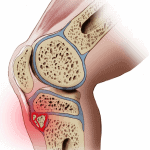

Osgood – Schlatter | Bài giảng CĐHA *

Osgood Schlatter là tình trạng viêm phì đại phần sụn lồi củ trước xương chầy, thường gặp ở trẻ thiếu niên nhất là trẻ nam, ưa hoạt động và có tốc độ phát triển cơ thể nhanh. Lực co kéo nhẹ song tái diễn nhiều lần gây bong một phần ở mỏm xương của lồi củ trước xương chày…